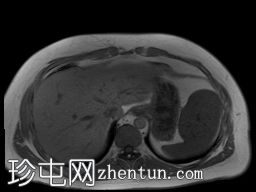

冠状位

T2加权像

T1低信号,T2低信号为主的脾脏肿块,内部可见T2高信号分隔,呈进行性强化。肿块中央可见星状瘢痕。

脾脏硬化性血管瘤样结节性转化(SANT),9.8 cm肿块

顾名思义,脾脏硬化性血管瘤样结节性转化(SANT)是一种纤维性血管病变。本病例展示了SANT的一些典型影像学特征,包括边界清晰的病灶,中央可见瘢痕,以及呈放射状进行性强化。这些特征使得术前MRI诊断较为明确。尽管SANT是一种良性病变,但大多数患者仍需行脾切除术以明确病理诊断。